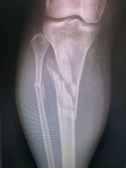

4.胫腓骨粉碎性骨折—MIPO技术